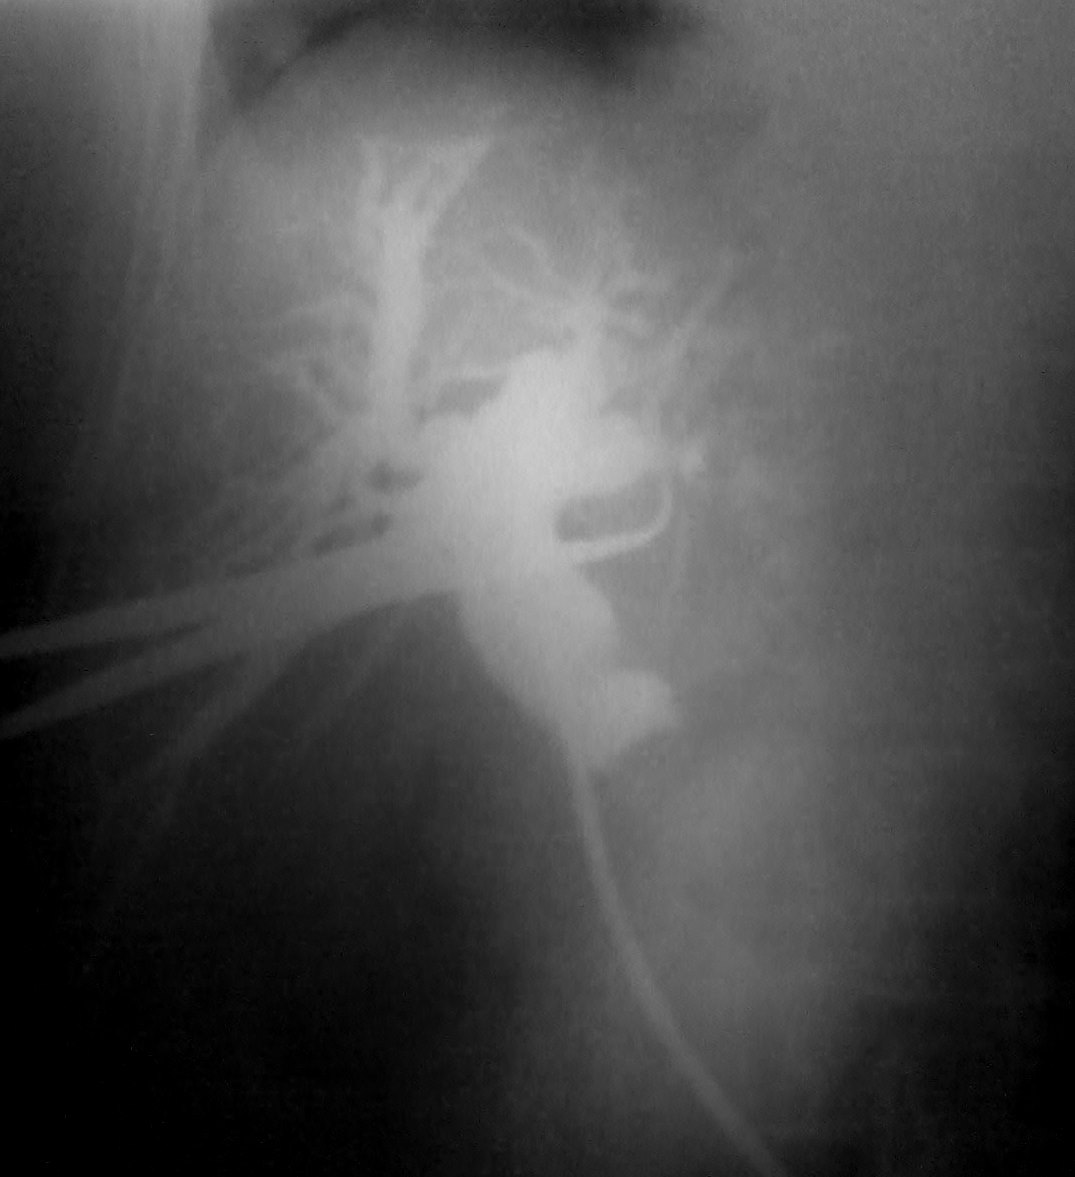

Фрагменты интраоперационных холангиографий. Вот первый случай...желтуха.... Вот второй случай....желтуха... Что скажете, коллеги....?